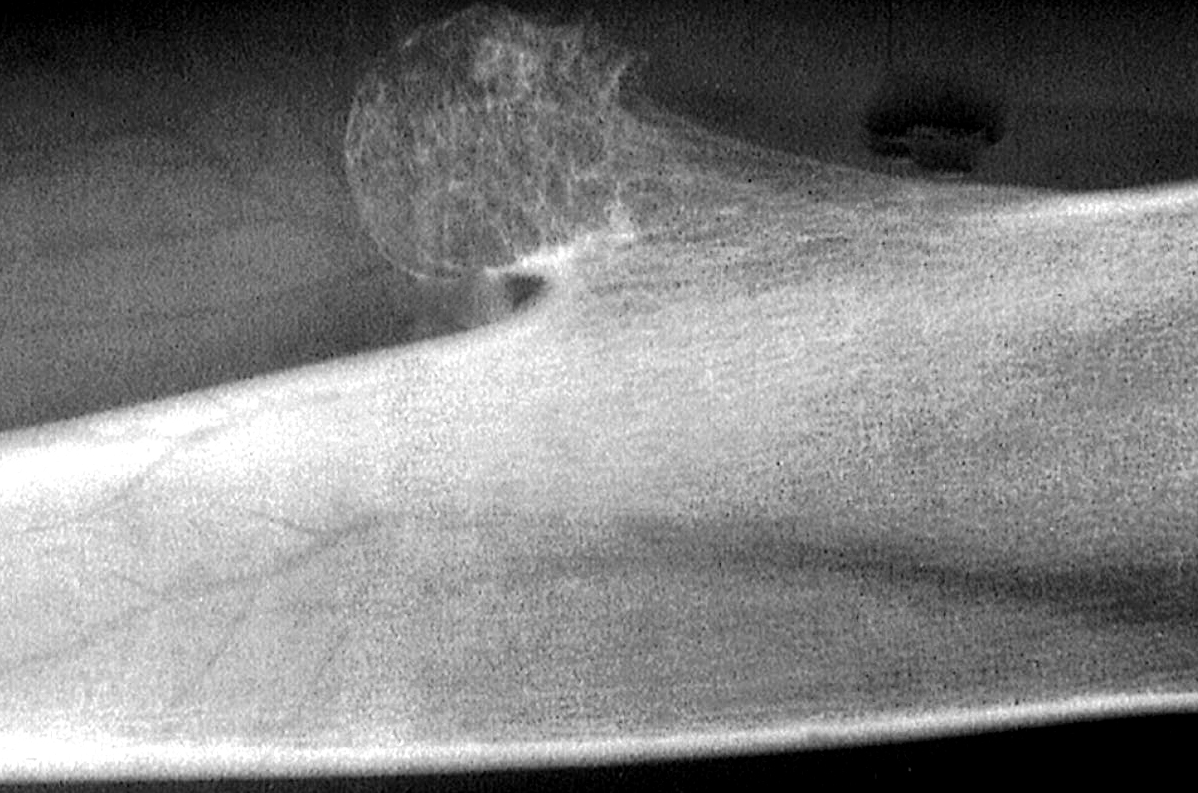

Radiology description

- Pedunculated or sessile

- Mature bony stalk continuous with the cortex; cancellous bone of stalk communicates with that of underlying bone

- Thin, lobulated cartilaginous cap, which may contain calcifications

- Growth perpendicular to the long axis of the bone

Radiology images